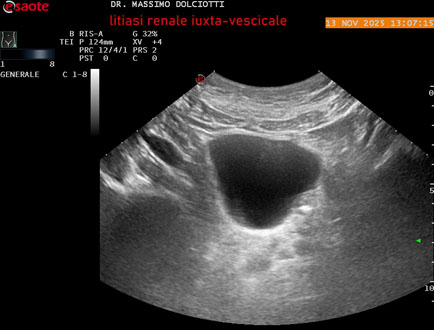

Data inserimento: 14/11/2025

Ecografia del: 13/11/2025

Strumento: Esaote MyLab Eight

Sonda: Convex Multifrequenza 1-8 MHz

Età Paziente: M 59 anni

Motivazione dell'esame: dolori al basso addome ed al fianco sinistro, comparsi la notte precedente.

Commento all'esame: le immagini ed il video documentano al rene sinistro, idronefrosi di 1°-2° grado, con presenza di immagine iperecogena, con cono d'ombra posteriore, allo sbocco dell'uretere sinistro, in sede iuxta-vescicale, delle dimensioni di 6,2 mm, con segno del Twinkling Artifact (o segno di Arlecchino), da ricondurre a litiasi.

Conclusioni: litiasi renale sinistra iuxta-vescicale (left juxta-vesical renal lithiasis).